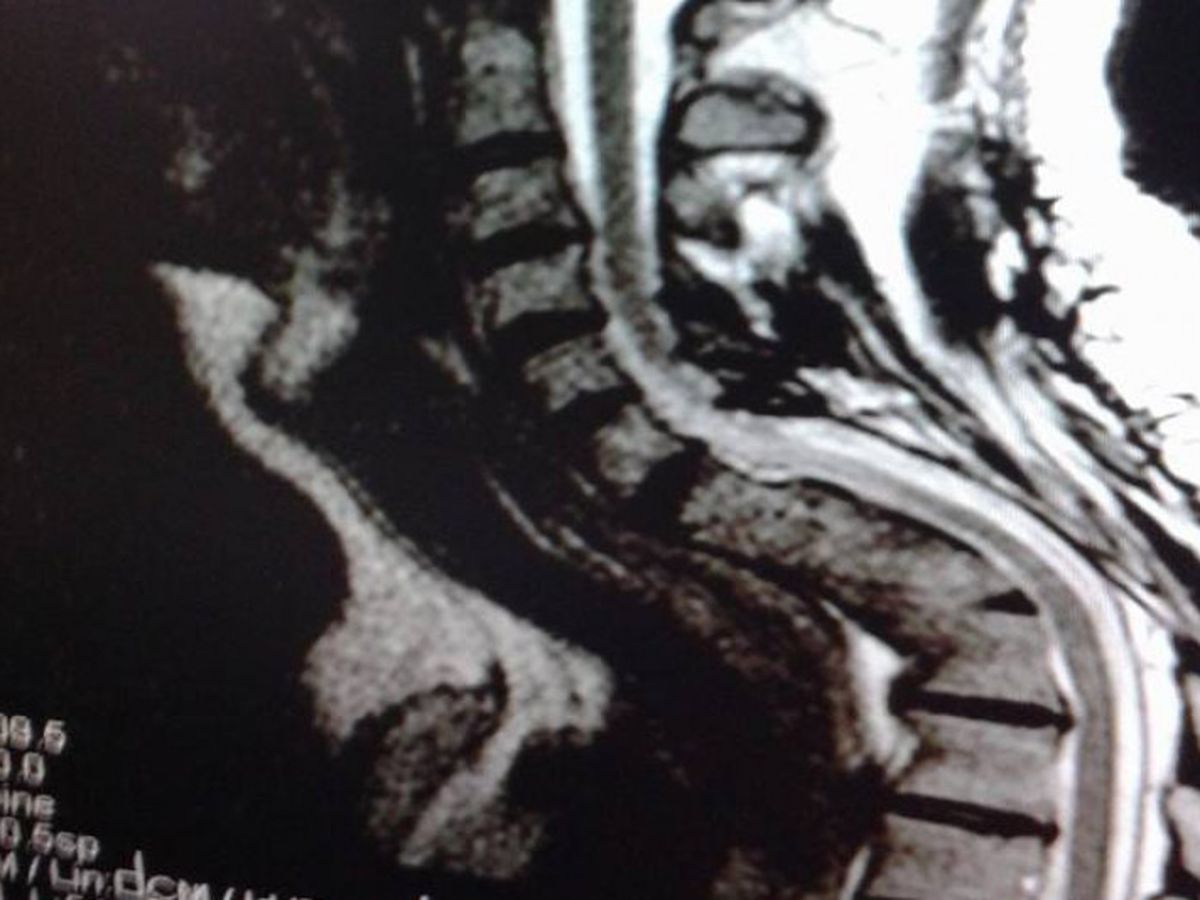

I developed a anneurismal bone cyst and a giant cell tumor on my spinal column . I went through 4 procedures to remove the tumor and cyst . The mass fusion did not hold properly and deformed but still my spinal cord is in good condition. Yes the picture is 100% real.